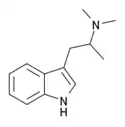

α-Alkyltryptamines are a group of substituted tryptamines which possess an alkyl group, such as a methyl or ethyl group, attached at the alpha carbon, and in most cases no substitution on the amine nitrogen.[17][18][19] α-Alkylation of tryptamine makes it much more metabolically stable and resistant to degradation by monoamine oxidase, resulting in increased potency and greatly lengthened half-life.[19] This is analogous to α-methylation of phenethylamine into amphetamine.[19]

N,N-Dimethyl-αMT (α,N,N-TMT) | (2-(1H-Indol-3-yl)-1-methyl-ethyl)dimethylamine | 4761-32-4 |